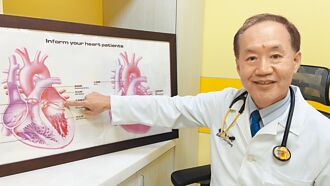

心臟病不可怕!達文西機械手臂手術助「心」病痊癒

以往的心臟傳統手術要將胸骨鋸開,胸前留下又長又明顯的疤痕,讓許多心臟病患避之唯恐不及。隨著醫學技術的進步,台中童綜合醫院於2012年引進「達文西機械手臂系統」,創傷小、恢復快,成為心臟科醫師及病患的一劑強心針,亦得到「心」病痊癒的理想成果。

彰化 黏液瘤亂漂釀胃痛 微創切除搞定

彰化縣62歲蔡姓婦人胃痛多年,以為是胃病,但經3次胃鏡檢查都查不出問題,直到5月間到員榮醫院檢查,才發現是左心房內有1顆2公分「黏液瘤」,隨著心臟收縮,在左心房與左心室之間漂來漂去,引起胃痛,由於黏液瘤隨時可能破裂,醫師表示,開心手術切除腫瘤是唯一治療選擇。

婦人胃痛多年查不出原因 轉診驚見「黏液瘤」在心臟漂浮

彰化縣1位62歲蔡姓婦人胃痛多年,以為是胃病,但經3次胃鏡檢查也查不出問題,直到今年5月間到員榮醫院檢查,才發現是左心房內有1顆2公分「黏液瘤」,隨著心臟收縮,在左心房與左心室之間漂來漂去,引起胃痛,由於黏液瘤隨時有破裂的可能,醫師表示,開心手術切除腫瘤是唯一治療的選擇。